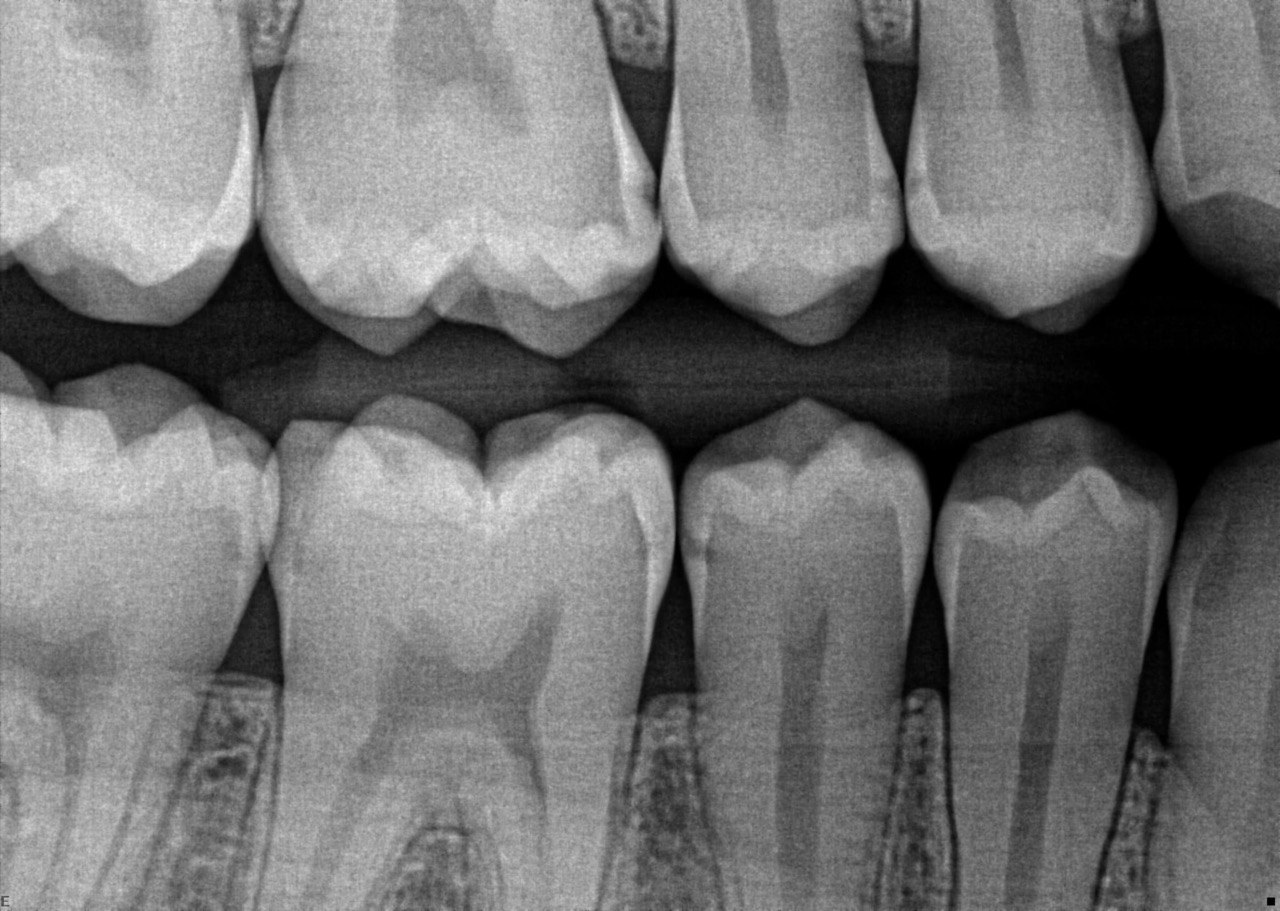

2. What surface require restoration?